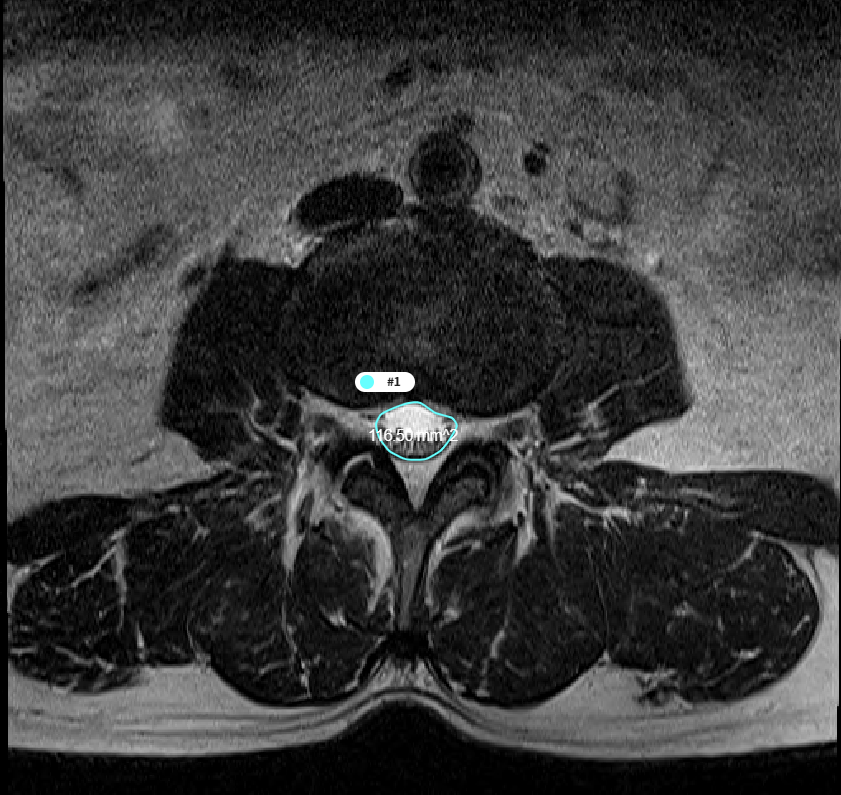

3. T2 Axial에서의 척수 영역 분할 및 면적 측정 모델

- 모델 학습

- 바이오 의료 영상 분야에서 분할을 목적으로 만들어진 모델을 사용하여 학습을 진행.

- Erode 및 Dilate, Median Blur를 이용해 이미지 후처리. Noise 및 Hole 제거

[T2 MRI에서 척수 영역 분할 모델 개요]

- 척추 면적 측정

- Dicom Header의 Pixel Spacing 정보를 통해 AI 결과에 대한 면적(mm2) 측정

[척추 영역 면적 측정]